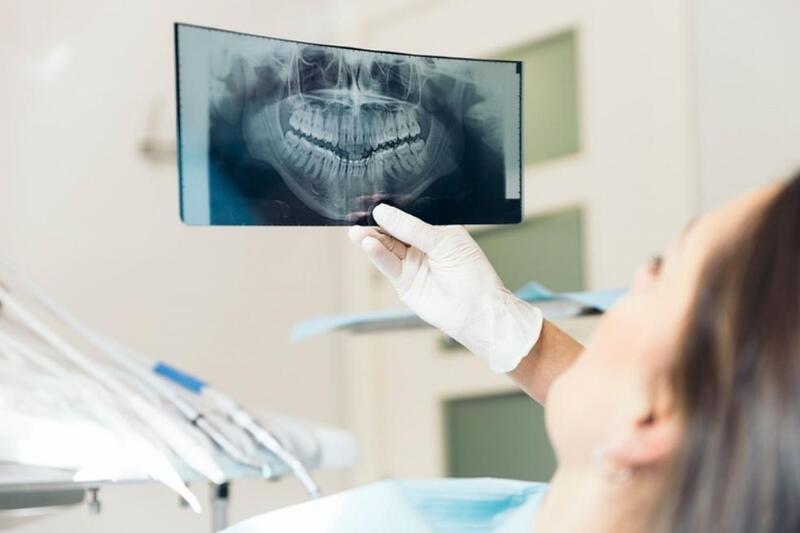

Bước 1: Thăm khám và chụp X-quang

Bác sĩ kiểm tra tình trạng răng miệng, đánh giá mức độ sâu răng, viêm tủy và cấu trúc chân răng. Chụp X-quang giúp xác định chiều dài ống tủy, vị trí viêm hoặc áp xe, hình dạng ống tủy cong hay thẳng. Đây là bước quan trọng để lên phác đồ điều trị chính xác.